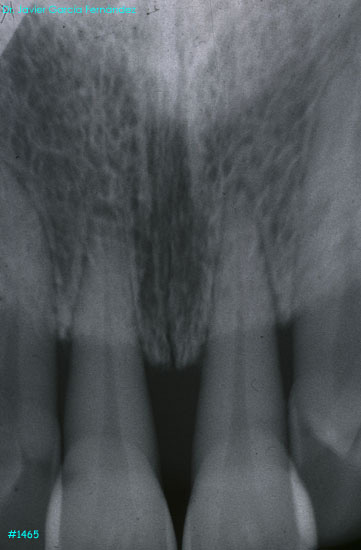

Atlas of Surgical Techniques in Periodontics. Chapter III. Atlas de Técnicas Quirúrgicas en Periodoncia